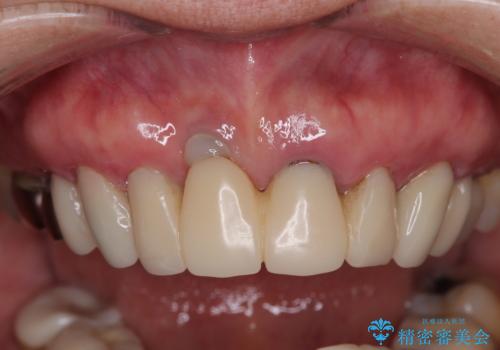

前歯のインプラントは埋入されたポジションが望ましい位置ではなく、インプラントを活用して段差を回収することは不可能と判断し、歯肉移植によりインプラントを隠して、ブリッジにて歯肉ラインを整えることとしました。

臼歯部の治療も必要と判断されましたが、前歯部を中心とした審美領域をオールセラミッククラウンによる補綴治療を行うこととしました。

帰国時のみの治療であったため、治療期間は長くなりましたが、最小限の来院回数で、気になっていた前歯をきれいに整えることができました。